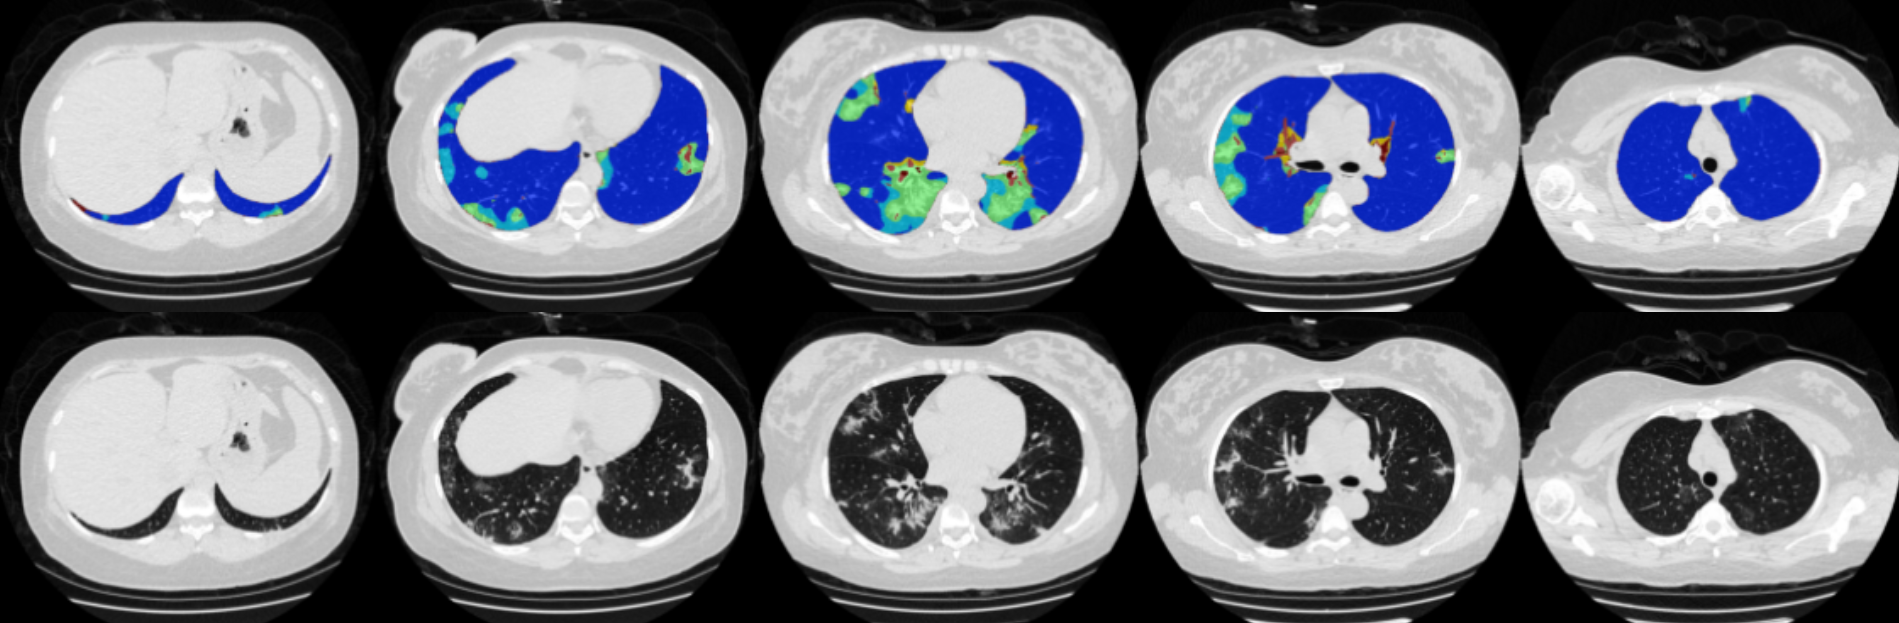

Predicting severity of disease based on imaging data

An example of how machine learning can use imaging data to predict individual disease course. Presented at the Annual Scientific Meeting of European Society of Thoracic Imaging 2022 in Oxford, UK by Jeanny Pan et al: Prediction of disease severity in COVID-19 patients identifies predictive disease patterns in lung CT. We could show that quantitative profiles are predictive for future disease course. Importantly, using not only the ratio of normal compared to non-normal tissue but instead the profile of individual disease patterns in the lung improved prediction performance. The study analysed data of 19 hospitals, with overall 329 COVID-19 patients. Based on the quanitative profile obtained from an initial CT scan comprising GGO, reticular pattern, emphysema, nodular pattern, coarse reticulation, effusion, pneumothorax, and consolidation the severity of disease was predicted.

Images: Johannes Hofmanninger, Jeanny Pan, Georg Langs

Images: MUW/Hofmanninger